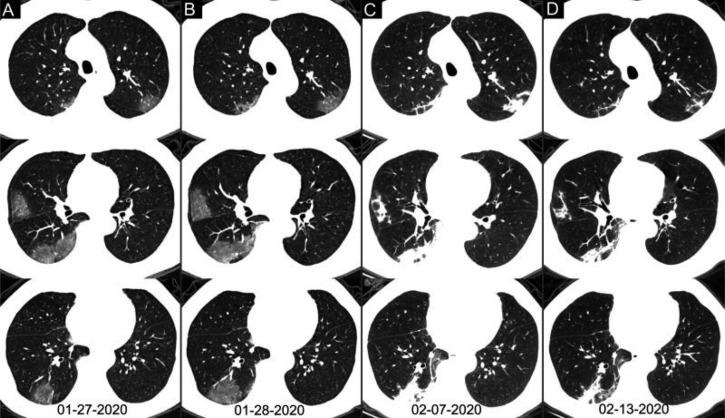

Background Chest CT is used in the diagnosis of coronavirus disease 2019 (COVID-19) and is an important complement to reverse-transcription polymerase chain reaction (RT-PCR) tests. Purpose To investigate the diagnostic value and consistency of chest CT as compared with RT-PCR assay in COVID-19. Materials and Methods This study included 1014 patients in Wuhan, China, who underwent both chest CT and RT-PCR tests between January 6 and February 6, 2020. With use of RT-PCR as the reference standard, the performance of chest CT in the diagnosis of COVID-19 was assessed. In addition, for patients with multiple RT-PCR assays, the dynamic conversion of RT-PCR results (negative to positive, positive to negative) was analyzed as compared with serial chest CT scans for those with a time interval between RT-PCR tests of 4 days or more. Results Of the 1014 patients, 601 of 1014 (59%) had positive RT-PCR results and 888 of 1014 (88%) had positive chest CT scans. The sensitivity of chest CT in suggesting COVID-19 was 97% (95% confidence interval: 95%, 98%; 580 of 601 patients) based on positive RT-PCR results. In the 413 patients with negative RT-PCR results, 308 of 413 (75%) had positive chest CT findings. Of those 308 patients, 48% (103 of 308) were considered as highly likely cases and 33% (103 of 308) as probable cases. At analysis of serial RT-PCR assays and CT scans, the mean interval between the initial negative to positive RT-PCR results was 5.1 days ± 1.5; the mean interval between initial positive to subsequent negative RT-PCR results was 6.9 days ± 2.3. Of the 1014 patients, 60% (34 of 57) to 93% (14 of 15) had initial positive CT scans consistent with COVID-19 before (or parallel to) the initial positive RT-PCR results. Twenty-four of 57 patients (42%) showed improvement on follow-up chest CT scans before the RT-PCR results turned negative. Conclusion Chest CT has a high sensitivity for diagnosis of coronavirus disease 2019 (COVID-19). Chest CT may be considered as a primary tool for the current COVID-19 detection in epidemic areas. © RSNA, 2020 ترجمه چکیده این مقاله به فارسی، در ضمیمه موجود است.

背景 胸部 CT 用于 2019 年冠状病毒病(COVID-19)的诊断,是逆转录聚合酶链反应(RT-PCR)检测的重要补充。目的 探讨胸部 CT 与 RT-PCR 检测在 COVID-19 诊断中的诊断价值和一致性。材料与方法 本研究纳入 2020 年 1 月 6 日至 2 月 6 日期间在中国武汉接受胸部 CT 和 RT-PCR 检测的 1014 例患者。以 RT-PCR 为参考标准,评估胸部 CT 对 COVID-19 的诊断性能。此外,对于多次 RT-PCR 检测的患者,分析 RT-PCR 结果(从阴性转为阳性,从阳性转为阴性)的动态转换与 RT-PCR 检测间隔为 4 天或更长时间的系列胸部 CT 扫描的一致性。结果 1014 例患者中,601 例(60%)的 RT-PCR 检测结果为阳性,888 例(88%)的胸部 CT 扫描结果为阳性。基于阳性 RT-PCR 检测结果,胸部 CT 提示 COVID-19 的敏感度为 97%(95%置信区间:95%,98%;601 例患者中的 580 例)。在 413 例 RT-PCR 检测结果为阴性的患者中,308 例(75%)的胸部 CT 检查结果为阳性。在这 308 例患者中,48%(308 例中的 103 例)被认为是高度疑似病例,33%(308 例中的 103 例)为可能病例。在对系列 RT-PCR 检测和 CT 扫描的分析中,初始阴性到阳性 RT-PCR 结果之间的平均间隔为 5.1 天±1.5;初始阳性到随后的阴性 RT-PCR 结果之间的平均间隔为 6.9 天±2.3。在 1014 例患者中,60%(57 例中的 34 例)至 93%(15 例中的 14 例)在初始阳性 RT-PCR 结果之前(或同时)有与 COVID-19 一致的初始阳性 CT 扫描。在 RT-PCR 结果转为阴性之前,24 例(42%)患者的随访胸部 CT 扫描显示改善。结论 胸部 CT 对 2019 年冠状病毒病(COVID-19)的诊断具有较高的敏感度。胸部 CT 可作为当前 COVID-19 检测在疫区的主要工具。 ©RSNA,2020